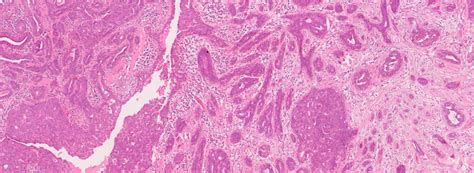

Alright, so let’s get real about why multimodal data is such a big deal when we’re talking about breast cancer prediction . Imagine you’re a detective trying to solve a case. Would you just look at one tiny clue and make your decision? Nah, you’d gather as much evidence as possible: witness statements, forensic reports, security footage, the whole nine yards. That’s exactly what multimodal learning does for breast cancer. Instead of just feeding a computer a stack of mammograms, we’re giving it a whole dossier of information. This can include radiological images like mammograms, MRIs, and ultrasounds, which are the traditional bread and butter of breast cancer screening. But it doesn’t stop there! We also throw in clinical data , which is all the juicy stuff from a patient’s medical record: their age, how many times they’ve given birth, whether they’ve had hormone therapy, their family history of cancer, and crucially, any known genetic mutations like BRCA1 or BRCA2. On top of that, we can even process textual data from doctors’ reports and pathology notes. Each of these data types brings something unique to the table. Images show us the physical manifestations of potential tumors or abnormalities. Clinical and genetic data give us insights into individual risk factors and predispositions. Textual data can capture nuanced observations that might not be immediately obvious in structured data fields. The magic happens when a deep learning model learns to correlate and integrate these different streams of information. It can identify patterns that a human might miss, or that are only apparent when multiple data points are considered together. For instance, a subtle abnormality on a mammogram might be flagged as higher risk if the patient also has a strong family history or a specific genetic marker. Conversely, a slightly denser area on an image might be considered less concerning if other factors indicate a low risk. This holistic approach is far more robust than relying on a single data modality. It reduces the chances of false positives (telling someone they might have cancer when they don’t) and false negatives (missing a cancer that is actually there), both of which have significant consequences for patients. By leveraging the power of diverse data sources, we can build prediction models that are more accurate, more personalized, and ultimately, more effective in the early detection and management of breast cancer. It’s like giving the AI a superpower to see the whole picture, not just a small slice of it, making it a true asset in our fight against this disease.